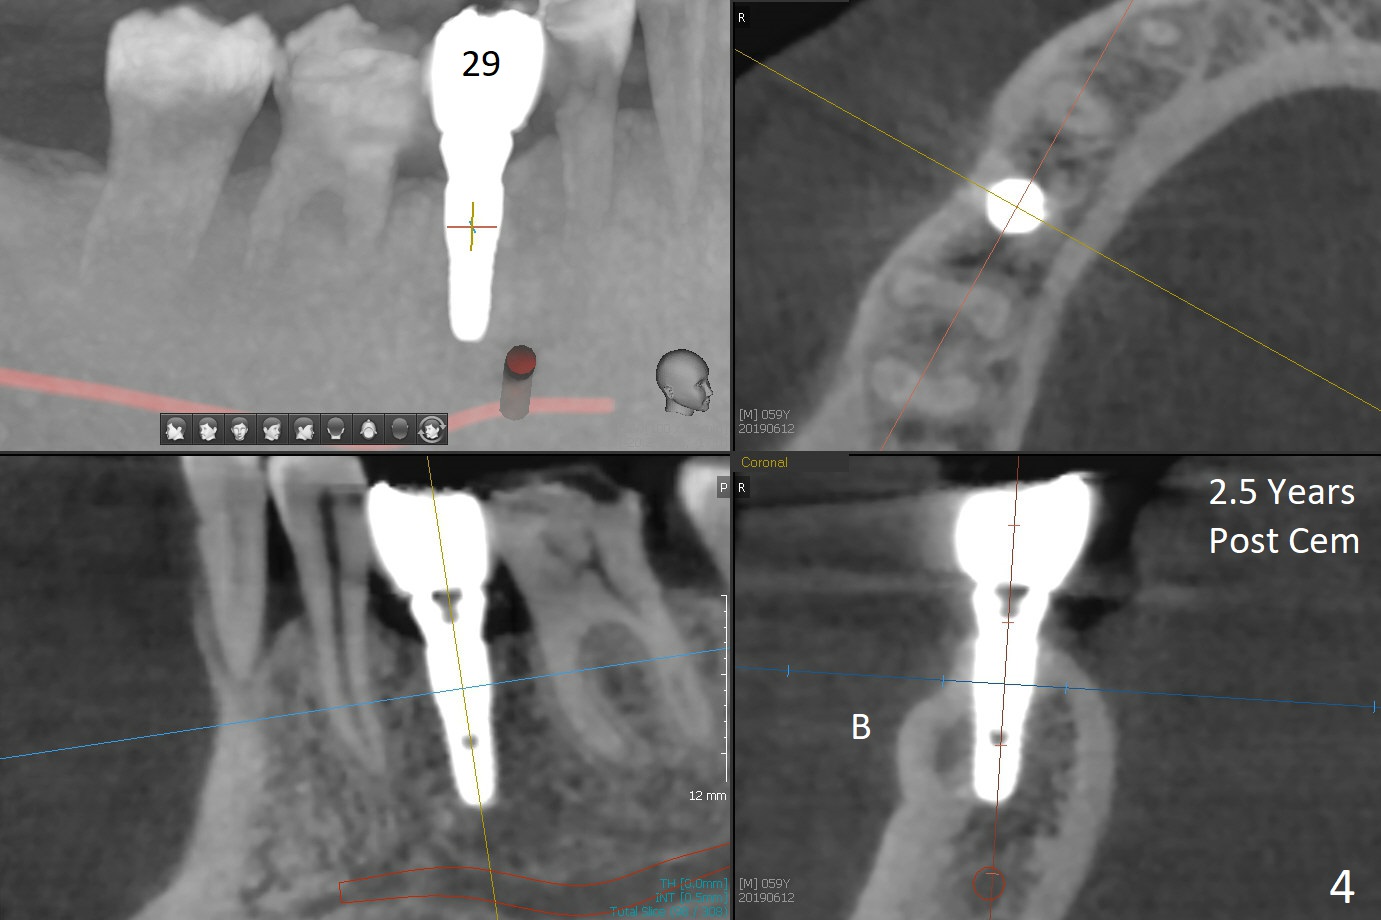

Partial edentulism with or without partial denture (especially in males) is more likely associated with implant failure than full dentition. Mr. Wang has lost several teeth (including #29, Fig.1) with secondary malocclusion, particularly supraeruption of the tooth #4. When a 3.8x10 mm submerged implant is placed with insertion torque >35 Ncm (Fig.2), an immediate provisional is selectively not placed to avoid micromovement. Instead, a healing abutment (5.2x5(3 mm) is placed immediately. For wound protection, periodontal glue and periodontal dressing are supplemented after suturing. Due to severe supraeruption of the tooth #4, the patient feels mild pain when he bites down heavily, a few hours postop. It is possible that the supraerupted tooth touches the periodontal dressing. The implant appears to be osteointegrated 4 months postop (Fig.3). A provisional is fabricated after placement of a cemented abutment (4.8x5(3) mm) to intrude the opposing tooth. There is no bone loss 2.5 years post cementation (Fig.4 CT).